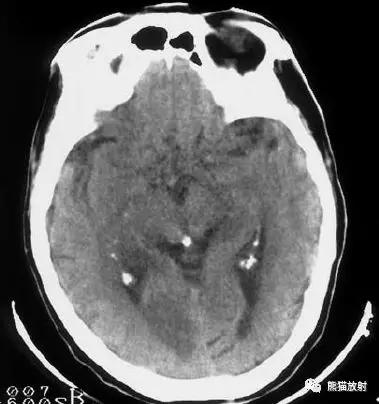

左侧大脑中动脉血栓形成(箭头)—— “大脑中动脉高密度征”,发病后不久行CT检查:相应的血管区域见缺血性病变。

右侧豆状核梗死灶(发病后15d),明显均匀强化。另左侧丘脑见腔隙性梗死灶。

左侧大脑中动脉区域大面积梗死,明显不均质强化。

右侧大脑中动脉区域脑梗死,脑回样强化。

左侧额叶脑梗死(发病后12d),由于模糊效应平扫显示不清,增强扫描脑回样强化。

右侧基底节区脑梗死,增强后病灶看上去有所缩小。

出血性脑梗死

上矢状窦血栓形成,呈高密度(箭头);并邻近脑实质内出血性脑梗死。